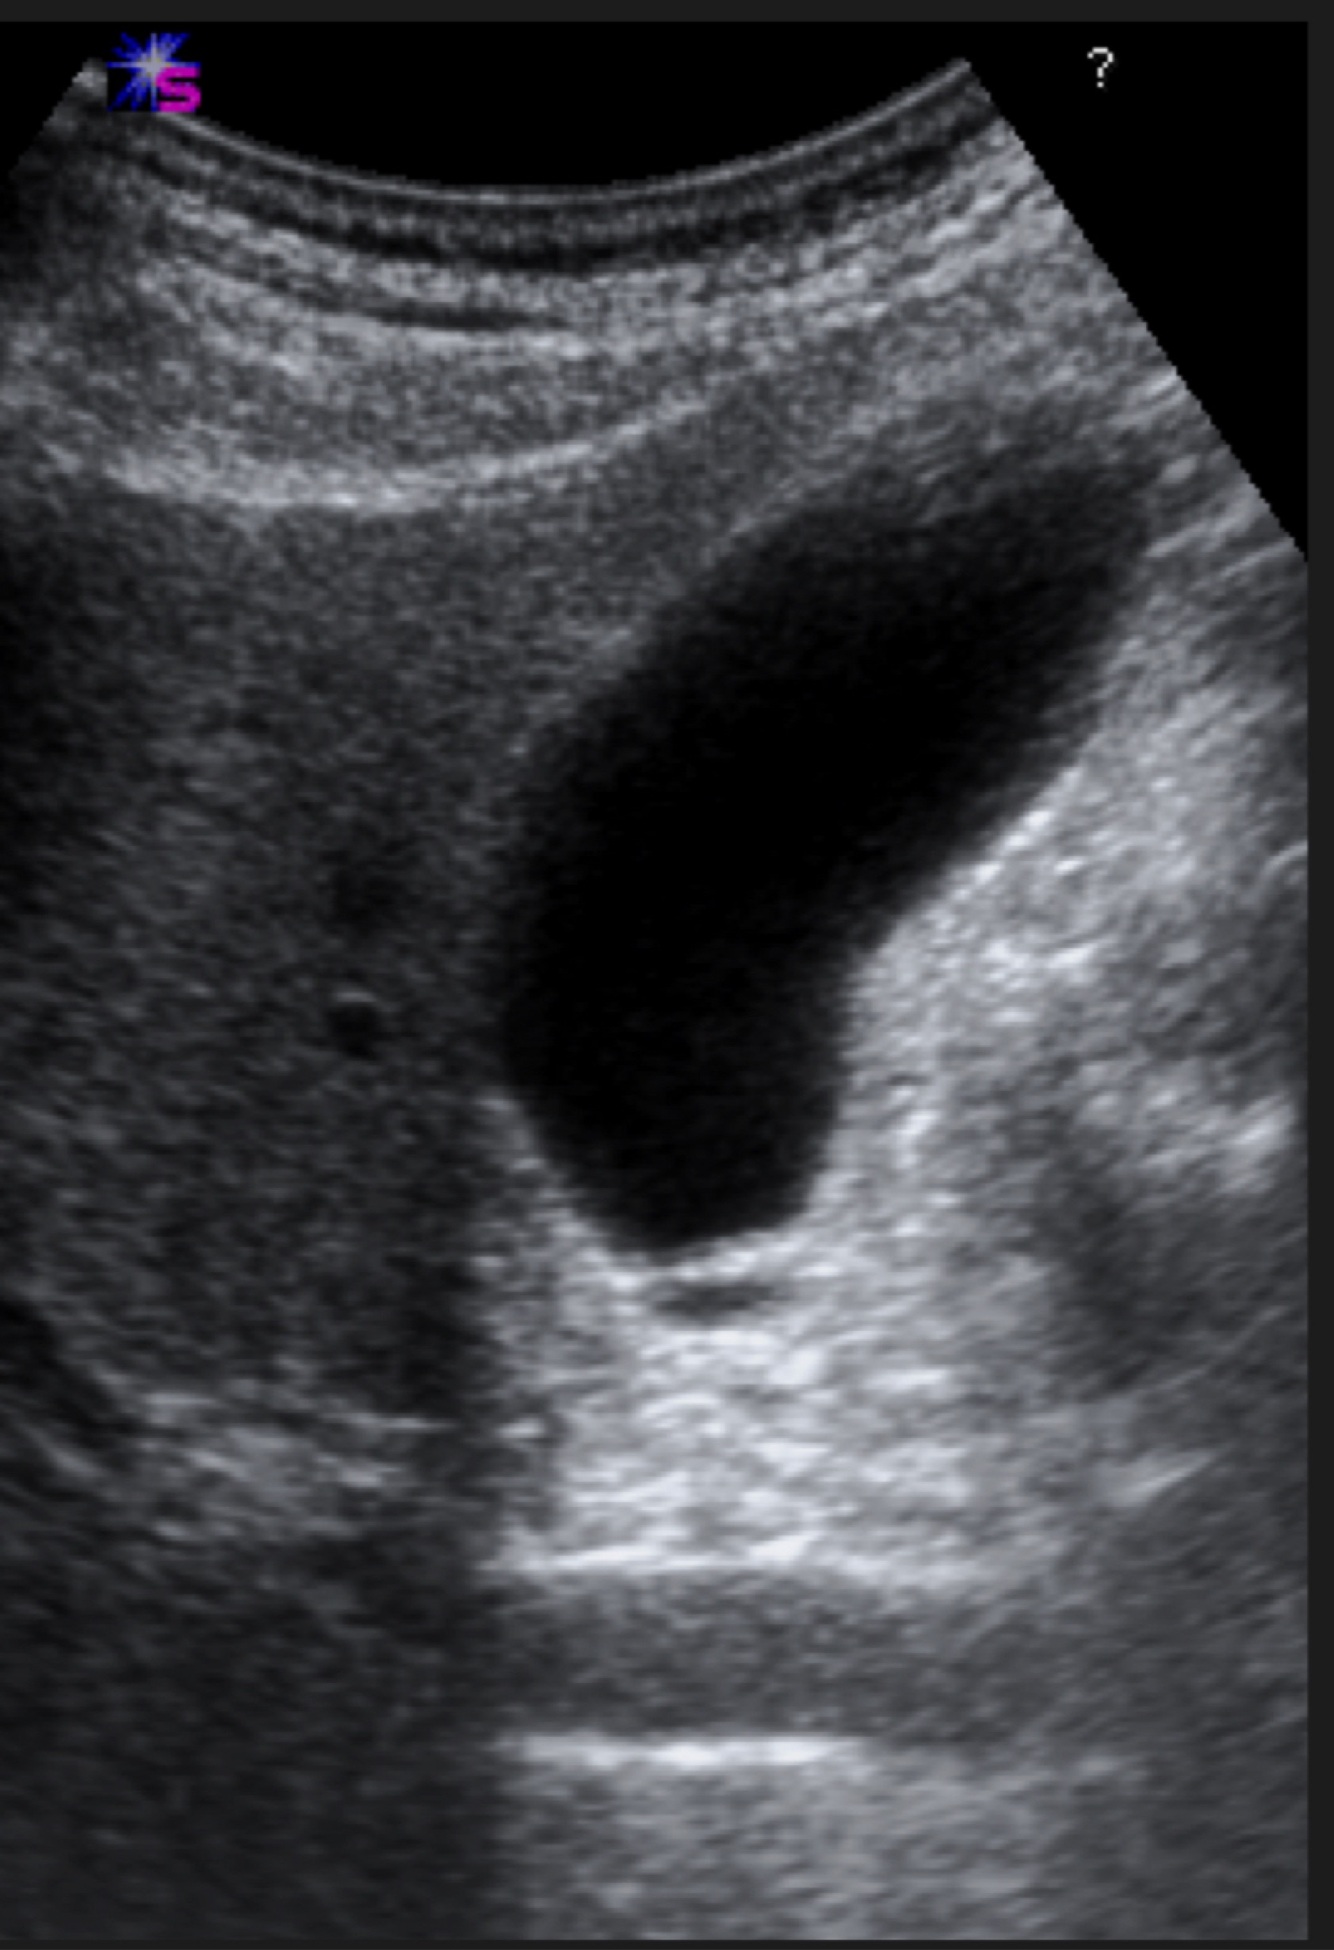

Q

A

Gallbladder (Ultrasound)

18

The gallbladder in ultrasound appears…

Hypoechoic